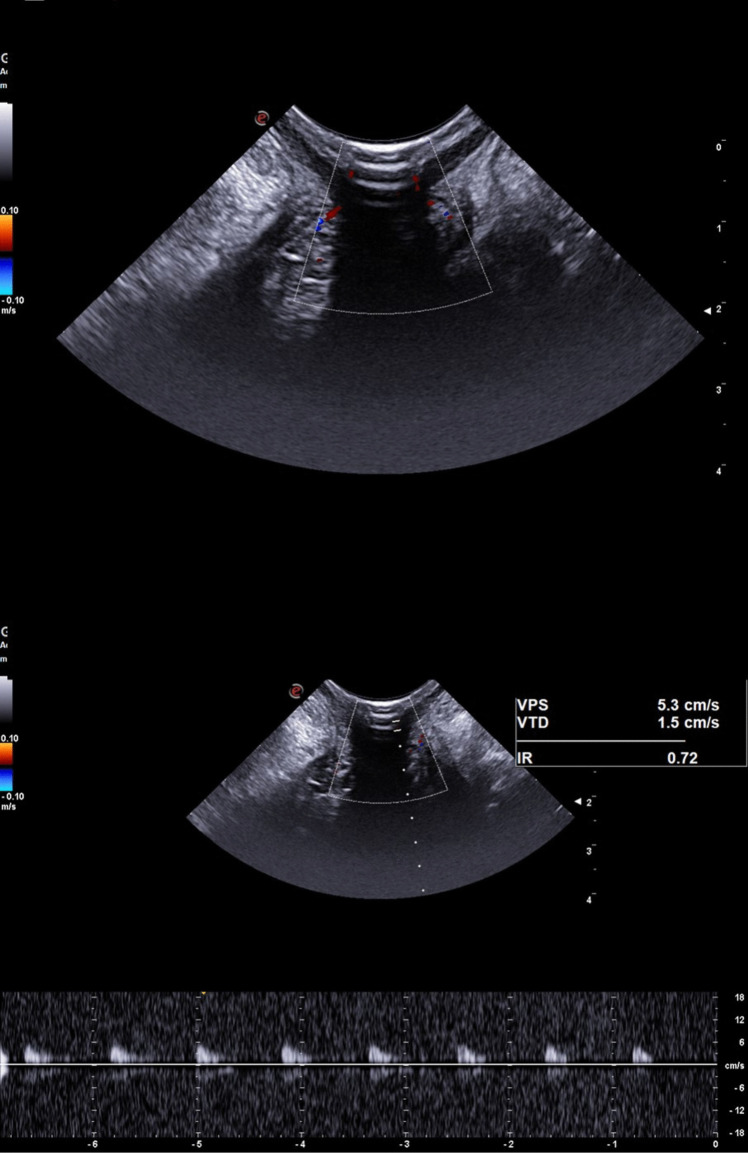

Methods: A prospective observational study was conducted on 50 healthy controls (HC) and 94 HD patients classified by Goligher grade. All underwent TPUS with Doppler assessment to record vascular patterns and quantify peak systolic velocity (PSV), end-diastolic velocity (EDV), and resistance index (RI).

Results: A vascular Doppler pattern was observed in 92.6% of HD patients vs. 50% of HCs (p < 0.001). HD patients showed significantly higher PSV (11.1 ± 3.6 cm/s vs. 8.3 ± 2.9 cm/s, p < 0.001) and RI (0.8 ± 0.1 vs. 0.7 ± 0.1, p = 0.015), with no significant difference in EDV. Among Goligher groups, grades III and IV showed significantly elevated PSV compared to HCs. No differences were observed in EDV or RI among subgroups.